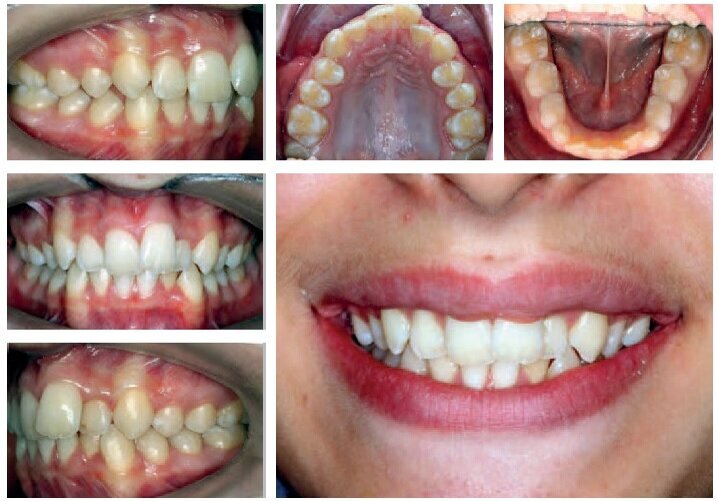

T.F. was 13 years old at the time of his first visit

Diagnosis

Class I, incisal-canine crowding in both arches

Class II long face syndrome, hyperdivergent

Retrusive chin

Presence of wisdom teeth buds

Treatment Plan

Non-extraction treatment

Alignment - levelling

Obtain a functional occlusion and accentuate the smile arc.

VISIT NO 6: POST-RETENTION PHOTOS +12 MONTHS